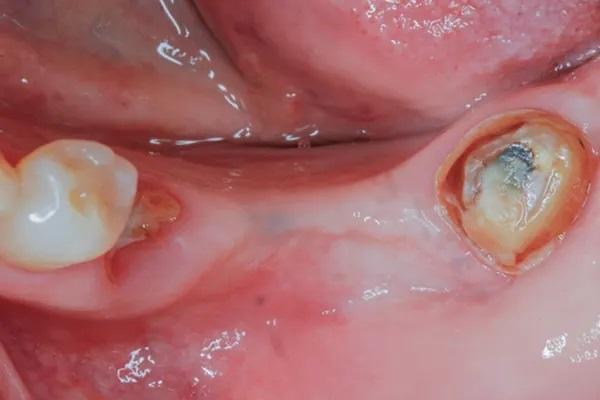

Женщина, 63 года, с неотягощенным анамнезом, явилась для восстановления левого квадранта нижней челюсти; в нем отсутствовали левые первый и второй моляр, а также были поражены второй премоляр и третий моляр, причем последний был наклонен мезиально из-за преждевременной потери второго моляра (Фото 2 и Фото 3). Было запланировано удаление разрушенных зубов с одновременным восстановлением гребня на участке дефекта от второго моляра до первого премоляра с помощью костного трансплантата и рассасывающейся коллагеновой мембраны.

Фото 2: (Случай 1) Вид c окклюзионной стороны перед операцией; обратите внимание на отсутствие первого и второго моляров нижней челюсти слева и связанную с этим потерю объема тканей.